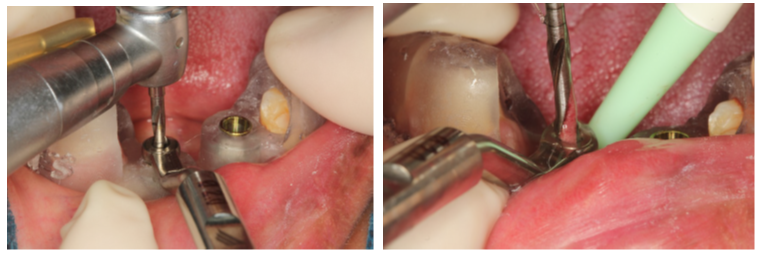

A cirurgia de reconstrução óssea estava contraindicada devido à qualidade ruim dos tecidos moles. Por conta disso, foi planejada uma cirurgia guiada para evitar o descolamento do tecido mole que fatalmente teria muita dificuldade para ter uma reparação satisfatória.

A escolha foi pelo implante Cone Morse Maestro, pois o osso era muito cortical e a macrogeometria do implante Maestro permite a colocação com um torque menor.

A cirurgia guiada foi fundamental na resolução desse caso, pois uma cirurgia com incisão e descolamento de tecido mole traria muitas dificuldades para a cicatrização.